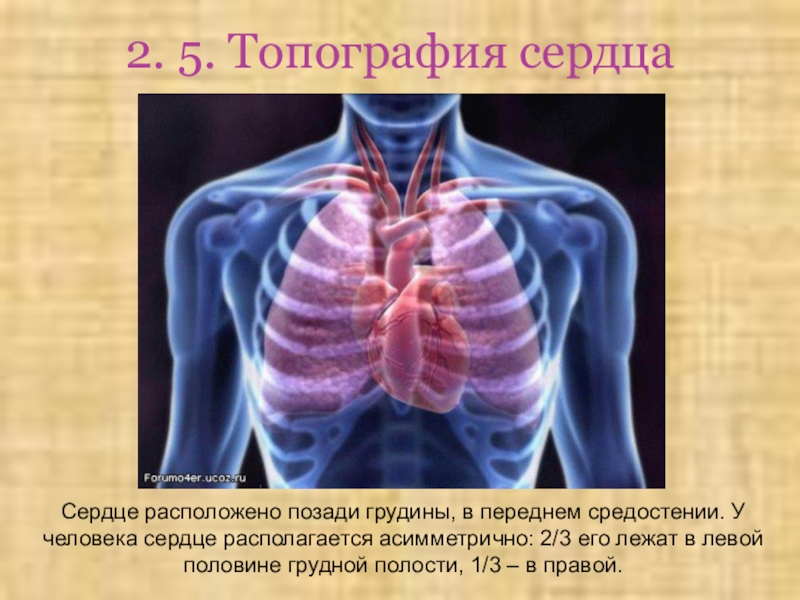

Анатомия Сердца: Расположение и Функции